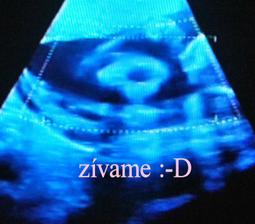

krasne 3D sono 🙂

Krasne foto dufam ze ti uz je lepsie mojko 🙂